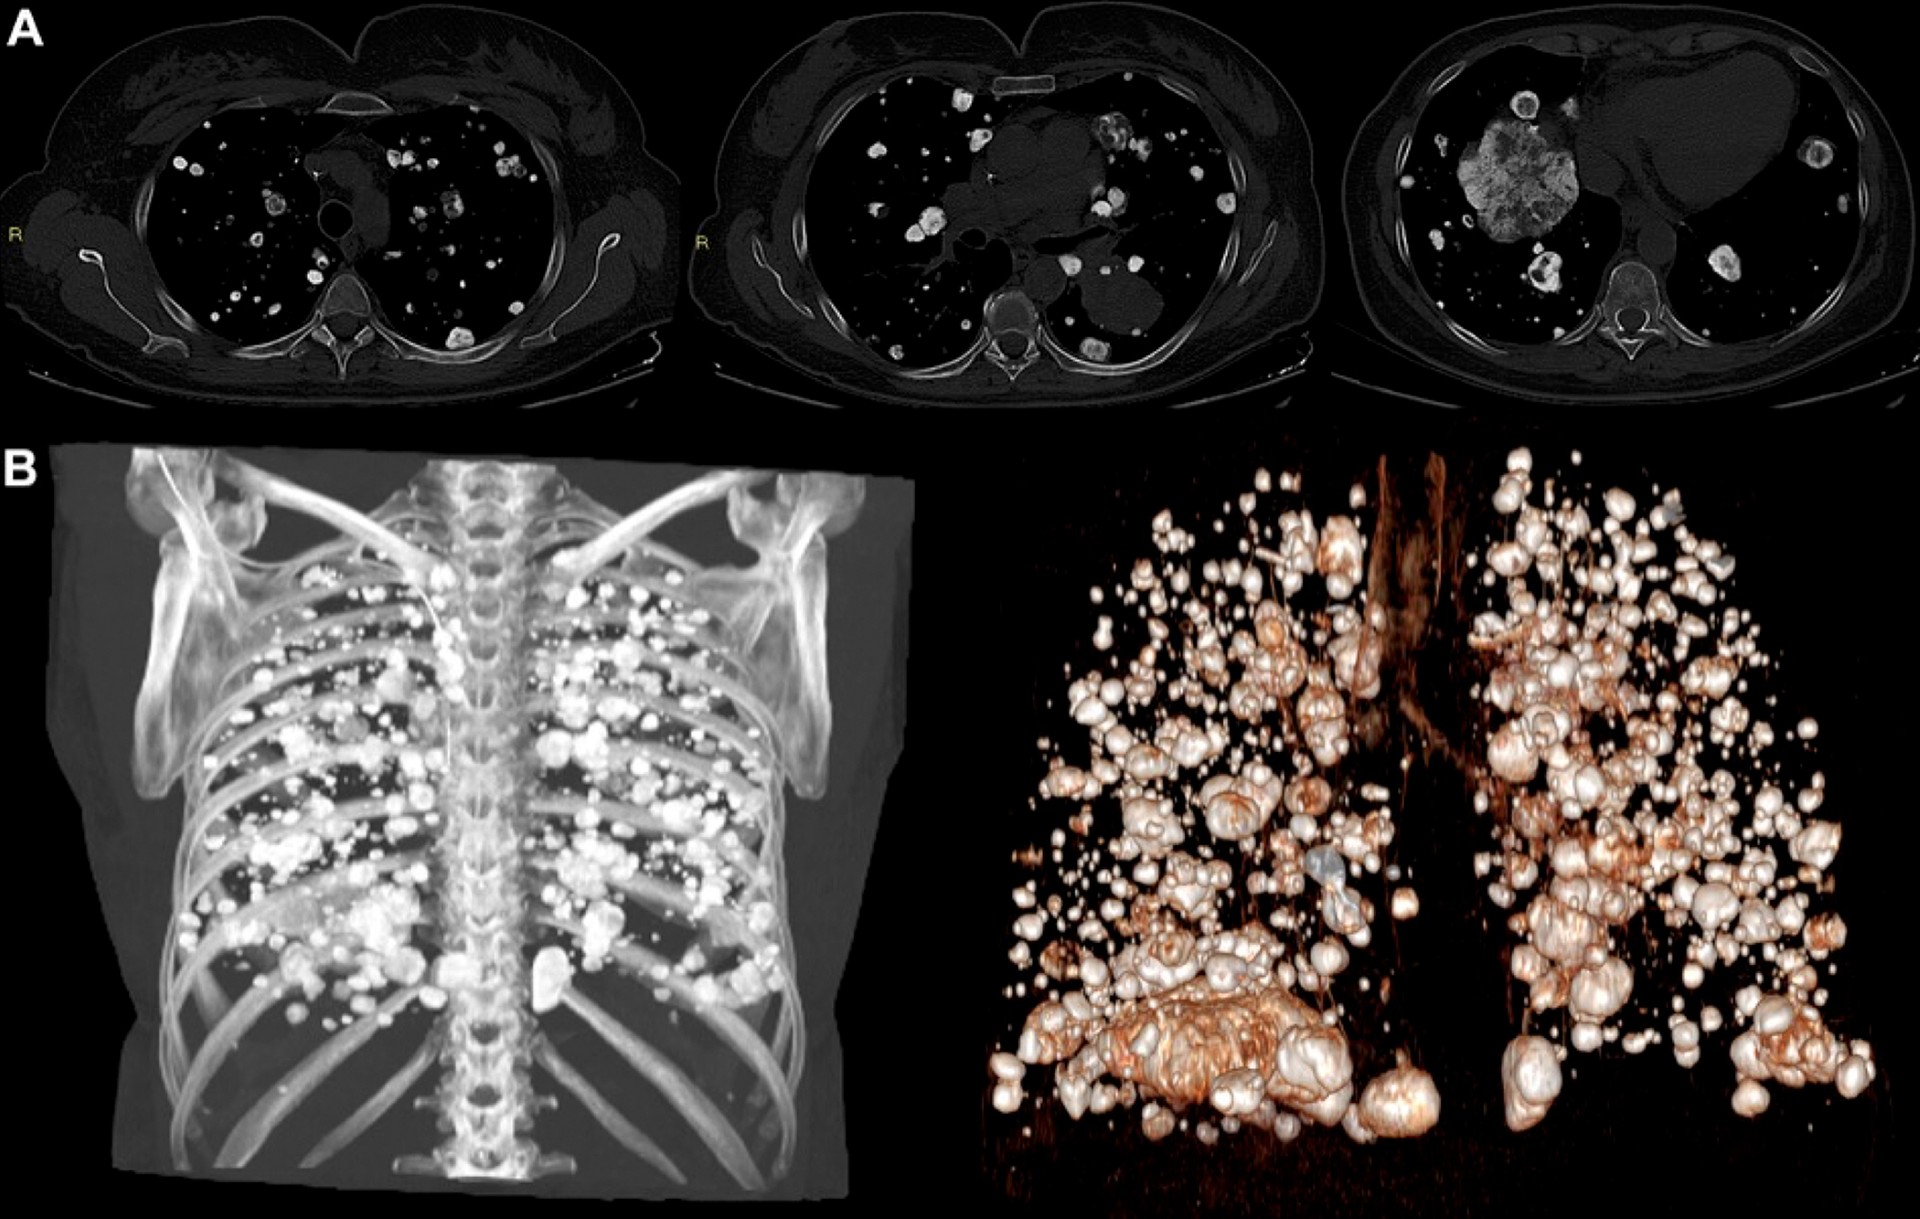

The winner of the 2025 Top Images in Radiology is “Cerebrofacial Arteriovenous Metameric Syndrome” by Dhairya A. Lakhani, MD, and Majid Khan, MD, which exceptionally shows this syndrome in a 15-year-old patient with an enlarging facial mass, visual disturbance, and epistaxis (1). The images demonstrated in exquisite detail the multitude of diffuse multifocal arteriovenous malformations of the intracranial and extracranial vasculature, including a massively dilated right ophthalmic vein, using cinematic and multiplanar rendering of CT angiograms of the head and neck. The article underscores the pivotal role of imaging in mapping these complicated embryologic defects of craniofacial vasculogenesis, demonstrating how a single imaging modality can elegantly capture and display the intricate appearance of this multifocal disease.

Figure 1: (A) Axial, (B) coronal, and (C) sagittal CT angiograms of the head and (D) axial, (E) coronal, and (F) sagittal cinematically rendered sections show diffuse, multifocal, large arteriovenous malformations of the brain, involving the supratentorial and infratentorial brain parenchyma, with multiple arterial feeders from the internal carotid, ex[1]ternal carotid, and vertebral arteries and prominent draining veins extending into both superficial and deep venous drainage systems. There is severe dilatation of the right superior ophthalmic vein, which receives increased flow from the vascular malformations via the cavernous sinus and drains into the right external and internal jugular veins via angular and facial veins. High vascular flow in the veins has resulted in remodeling and widening of diploic spaces of the frontal calvarium and the right orbit, with resultant mild right proptosis. Multiple arteriovenous malformations are also present in the scalp—the largest in the occipital region, receiving arterial flow from the external carotid artery via the occipital artery and draining into the external jugular vein via the occipital vein. ©RSNA 2025